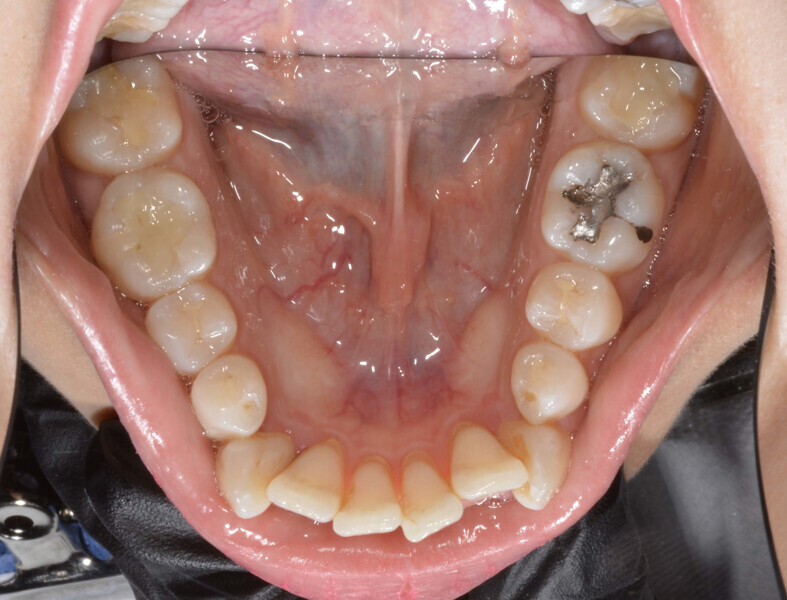

A 35-year-old female patient presented with crowding, muscle and joint pain, and headaches upon awakening. Examination found a skeletal Class I with crowding and bimaxillary protrusion. Facial examination showed a convex profile with protruded lips and a square face shape, intensified on smiling (Figs. 1–4). She reported bruxism, and bilateral masseteric hypertrophy was observed, but there was no alteration of the temporomandibular joints.

Before the aligner treatment began, the maxillary and mandibular second premolars were extracted to create space. With orthodontic treatment, distalisation of the anterior teeth was achieved by employing maximum mandibular anchorage and moderate maxillary anchorage (Figs. 5–7). At the end of the treatment, a stable bilateral Class I occlusion had been achieved, as well as normal inclination and retrusion of the anterior teeth, consequently improving the profile (Figs. 8–10).